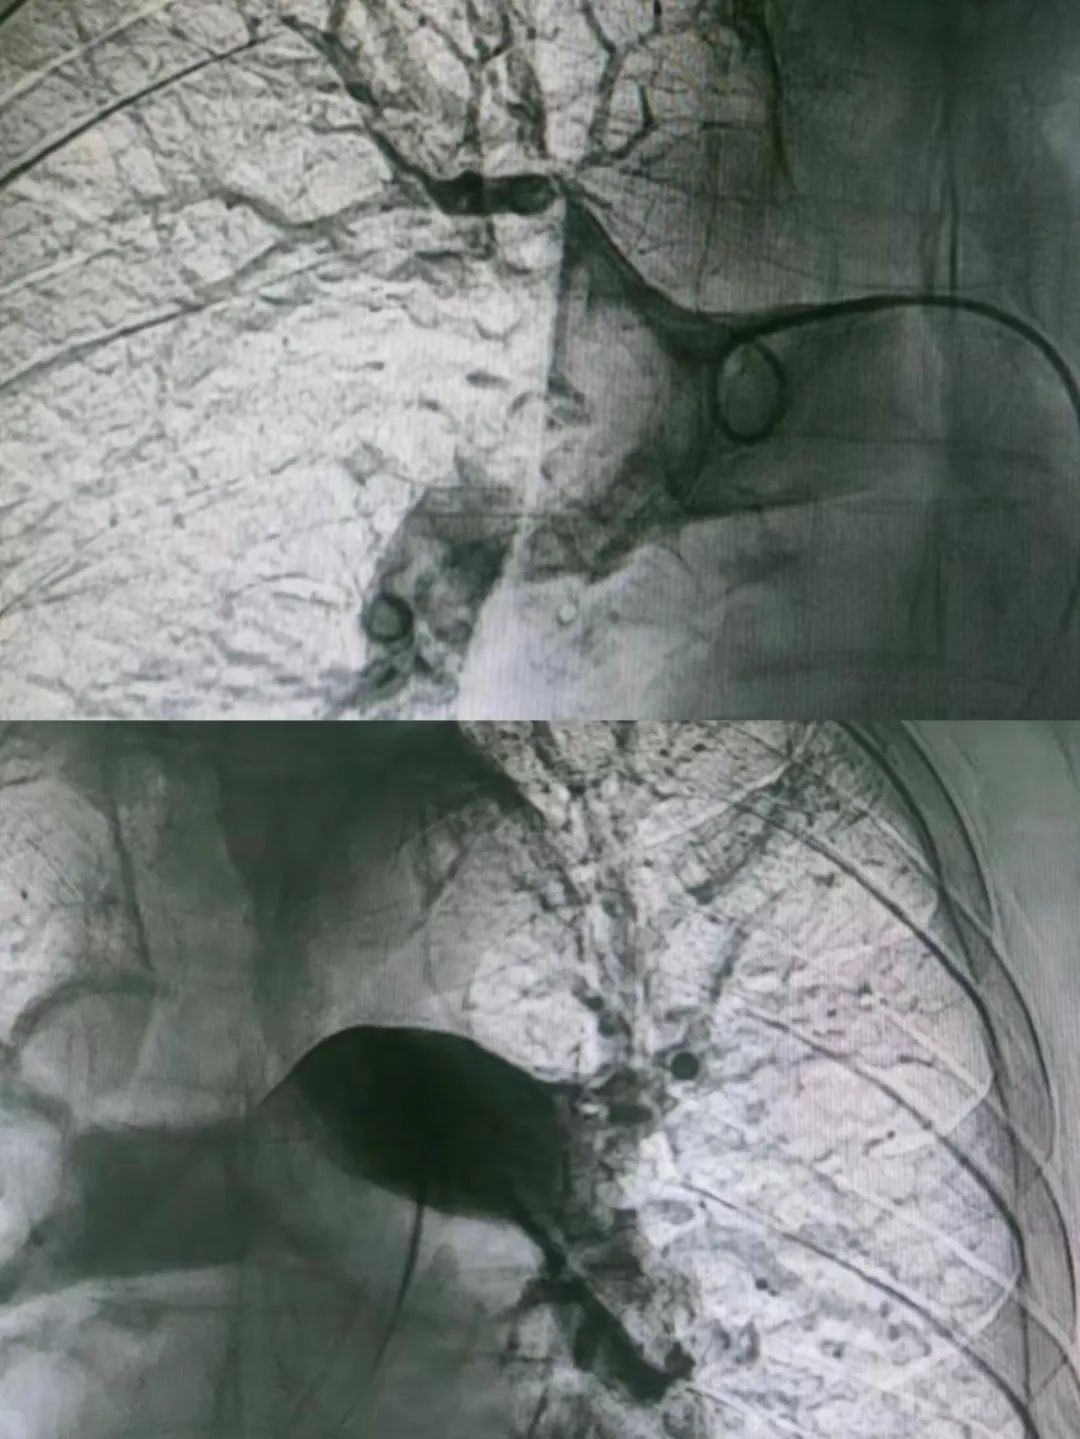

患者金某,女,61岁。主因“突发心悸伴晕厥3小时”,查体见左下肢肿胀,SaO295%,心电图提示“SIQIIITIII,不完全性右束支传导阻滞,ST段下移”;肌钙蛋白I0.248ng/ml,血浆D-二聚体5703ng/ml,考虑急性肺动脉栓塞或急性冠脉综合征;因患者存在过敏史,无法完成肺动脉联合冠状动脉CTA检查,胸痛中心与血管肿瘤介入科VTE项目联合会诊,拟行心肺联合造影检查及介入治疗,结果提示左冠前降支轻度狭窄,双侧肺动脉栓塞,给予肺动脉尿激酶溶栓、静脉滤器置入,术后患者病情平稳症状好转,手术由胸痛中心郑凯、巴根那联合血管肿瘤介入科梁羽、那日苏等几位医师共同完成。

患者李某,男,70岁。既往高血压病史3年。主因“头晕、气短3天”,查体见左下肢稍有肿胀,SaO291%;VTE绿色通道行CTPA提示大面积肺栓塞,血浆D-二聚12.12ng/ml;考虑急性肺动脉栓塞;立即为其行肺动脉造影、下腔静脉滤器置入、肺动脉溶栓药物灌注术进行治疗,术后SaO295%。手术由血管肿瘤介入科魏东升主任、梁羽、那日苏几位医生合力完成。以上2例患者经术后予抗凝溶栓治疗,均已康复出院。